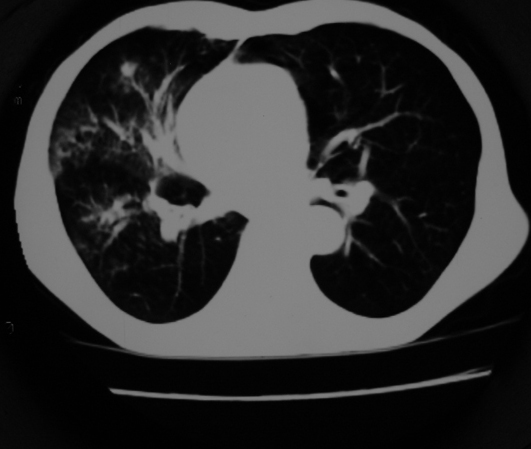

以下是引用同在2007-1-27 14:13:00的发言:[br]支持右侧中央型肺癌伴阻塞性病变.

以下是引用zjzjr在2007-1-27 16:56:00的发言:[br]支持右肺中心型肺癌伴阻塞性肺炎.